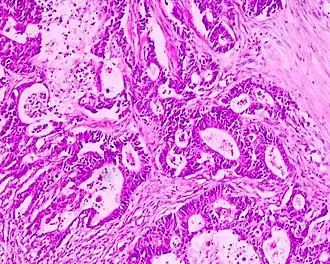

Naast beeldvormend onderzoek zal er ook altijd pathologisch onderzoek nodig zijn. Hierbij kan gekeken worden naar de kankercellen zelf (cytologie) en naar het verband tussen de kankercellen en de omgeving waarin ze liggen (histologie). Dit materiaal kan worden verkregen middels puncties met een naald of via operatieve verwijdering. Vaak wordt ook operatief gekeken hoe ver het kankerproces is uitgebreid in het lichaam (lymfeklieren en metastasen op afstand).

Pathologie (soorten tumoren)

Er zijn vijf soorten maligne tumoren:

- carcinomen uit epitheel;

- sarcomen uit steunweefsel;

- maligne lymfomen uit lymfeweefsel;

- blastomen uit cellen van zich ontwikkelend weefsel;

- kiemceltumoren uit kiemcellen.